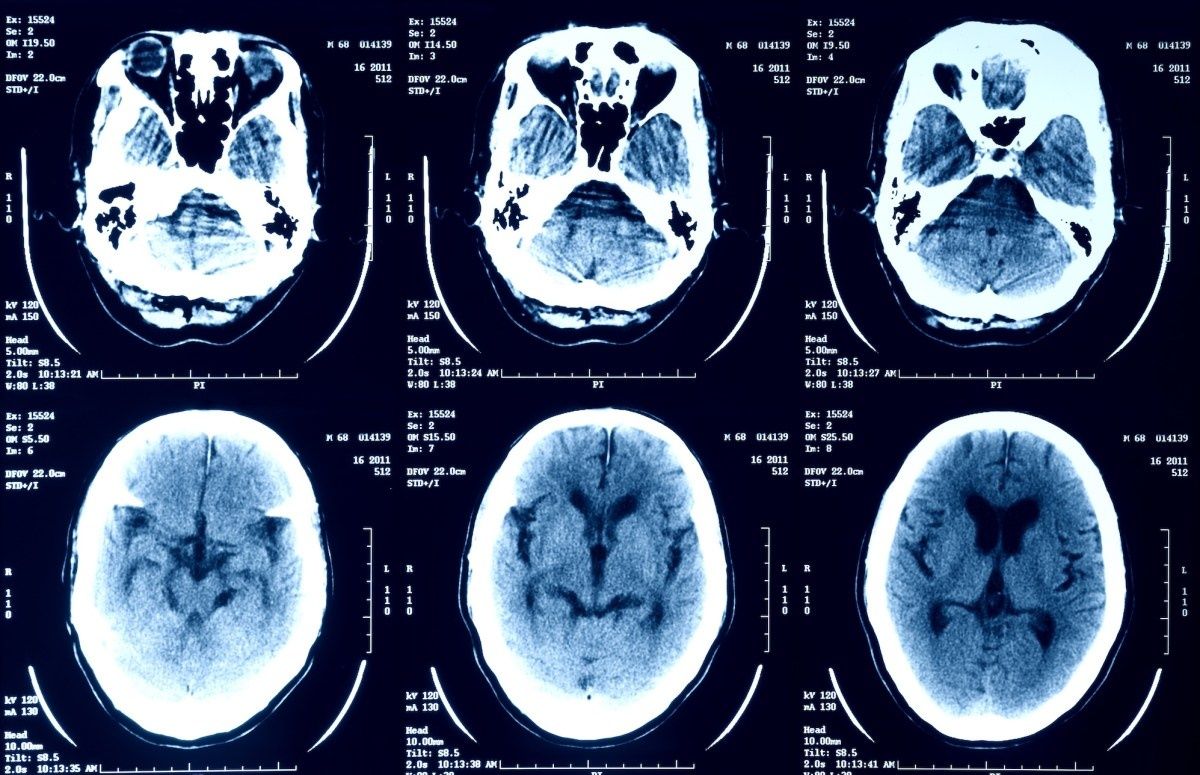

Healthcare analytics firm Episource has begun notifying millions of individuals that their sensitive medical information was compromised in a recent cyberattack. The breach, which the company disclosed in regulatory filings this week, exposed patient records containing diagnoses, treatment histories, and insurance details.